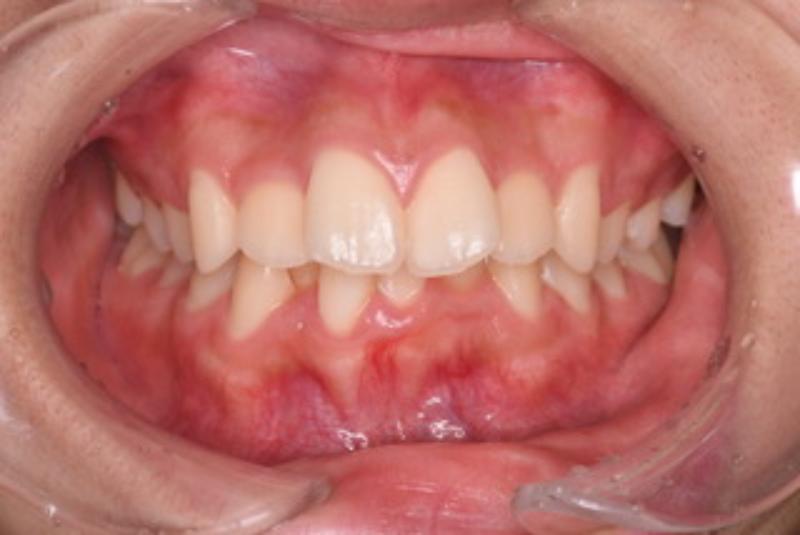

【術前】 【術中】 【術後】

前歯のガタつきと口元を引っ込めたい(口ゴボ)のため受診された16歳女性の方は、下顎前歯部のガタつきと、上顎の狭窄及び下顎の後退が予測されました。上顎の前歯をマウスピース矯正で引き込むだけでなく下顎を正常な位置まで戻すことで噛み合わせを再構築し、前歯のガタつきを抜歯する事なく改善できたそうです。

【治療部位】上顎・下顎

【治療期間】36ヶ月間

【治療回数】30回

【リスク】矯正しても横顔(口ゴボ)が改善しない事がある

【治療費用】精密検査:50,000円(税込)

一時矯正:900,000円(税込)

調整:0 円

合計:950,000円(税込)